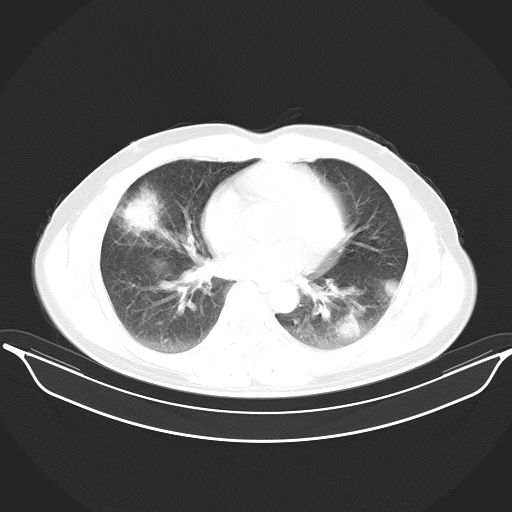

标题: CT25490:男,40岁,体检发现;无其它不适。 [打印本页]

标题: CT25490:男,40岁,体检发现;无其它不适。

考虑右下肺周围性肺癌并肺内多发转移,纵隔淋巴结转移!

支持 !考虑右下肺周围性肺癌并肺内多发转移,纵隔淋巴结转移,(气管前腔静脉后,隆突下,主动脉弓下都有了)